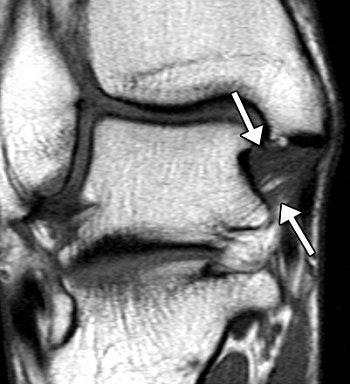

| Posterior TTL (posterior portion of the deep layer of the MCL complex) in asymptomatic 28-year-old woman. Above, corresponding drawing. Middle, T1-weighted coronal MR image (572/14). Below, T2-weighted coronal MR image (4130/86). The posterior TTL (arrows) originates from the upper segment of the posterior surface of the anterior colliculus, the intercollicular groove, and the anterior surface of the posterior colliculus. The fibers insert onto the medial surface of the talus. A typical striated appearance is seen on both T1- and T2-weighted images. |

According to the results, the anterior TTL, posterior TTL, TNL, TSL, and TCL were best seen on the coronal images. An inhomogenous pattern of the anterior TTL on T1-weighted images was seen in 21% of the subjects younger than 45 years and in 67% of those over age 45.

For the posterior TTL, the signal-intensity pattern was striated in 89% of the volunteers. It was also broader distally and had well-delineated borders. The authors suggested that the absence of striation in younger patients could be taken as a sign of possible TTL abnormality.

On T2-weighted images, the TSL had low signal intensity with a homogenous signal intensity pattern. For the TCL, the signal intensity was intermediate on T1-weighted images. The posterior TTL had a mean thickness of 8.2 mm, while the TCL had a mean thickness of 1.2 mm.